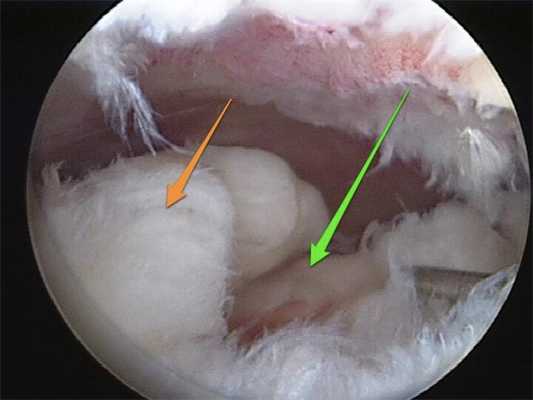

- Артроскопия. Инвазивная процедура, требующая проникновения в суставную полость. Позволяет изучить морфологию хряща и уточнить диагноз при помощи прицельной биопсии. Используется редко.

Изображение полости сустава.

В целях высокоинформативной диагностики специалист через микропортал вводит рабочую трубку устройства внутрь сустава, в которую вмонтированы система ультрасильных линз, мощный световой источник и видеозаписывающая цифровая техника. Все структуры, что «видит» артроскоп, визуализируются на экране в «живом» виде, причем изображение поступает в многократно увеличенном формате. Врач может найти точное расположение травмы или дегенеративных изменений, установить характер патологии, степень тяжести и принять меры.